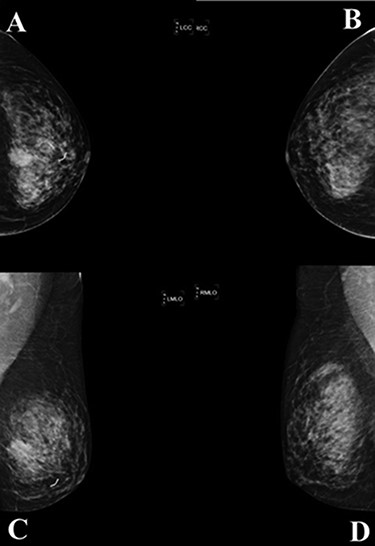

(A) Histologic examination showed the neoplastic cells predominantly arranged in a solid growth pattern (100×). (B) The true glandular spaces lined by luminal-type epithelial cells (600×). (C) The pseudolumens containing watery basophilic mucopolysaccharides basement membrane-like materials rimmed myoepithelial cells (400×). (D) Intraductal components composed of a dual population as the invasive areas (600×)

complex. The left axillary lymph node was found to measure 1 cm after palpation. A mammogram revealed an ill-defined mass at sub-areolar on left breast with angulation 2.3 × 1.9 cm, without suspicious microcalcification or architectural distortion (Fig. 1). Core needle biopsy revealed invasive ductal carcinoma (IDC). Immunohistochemical study (IHC) showed Estrogen receptor (ER), Progesterone receptor (PR), and Human epidermal growth factor receptor 2 (HER2) negative. Fine needle aspiration of left axillary lymph node revealed poorly differentiated metastatic lymph nodes. Metastatic workups were unremarkable. Left lumpectomy and axillary lymph nodes dissection were performed. The final pathology reported ACC measuring 3.5 cm in greatest dimension, lymphovascular invasion, presenting with DCIS, comedonecrosis type, high grade nuclei, microcalcification, all margins are negative for malignancy (Fig. 2). IHC showed CD117 and CK7 positive for malignant ductal cell of tumor, CK5/6 and p63 positive for myoepithelial cells within the tumor. ER, PR and HER-2 were negative. Ki-67 was strongly positive 3 + of nuclear staining, 30% of neoplastic cells (Fig. 3). One of 21 lymph nodes demonstrated metastatic ACC with extranodal extension (Fig. 4). Metastatic part is 0.9 cm in greatest dimension. Postoperative adjuvant chemoradiotherapy was given.